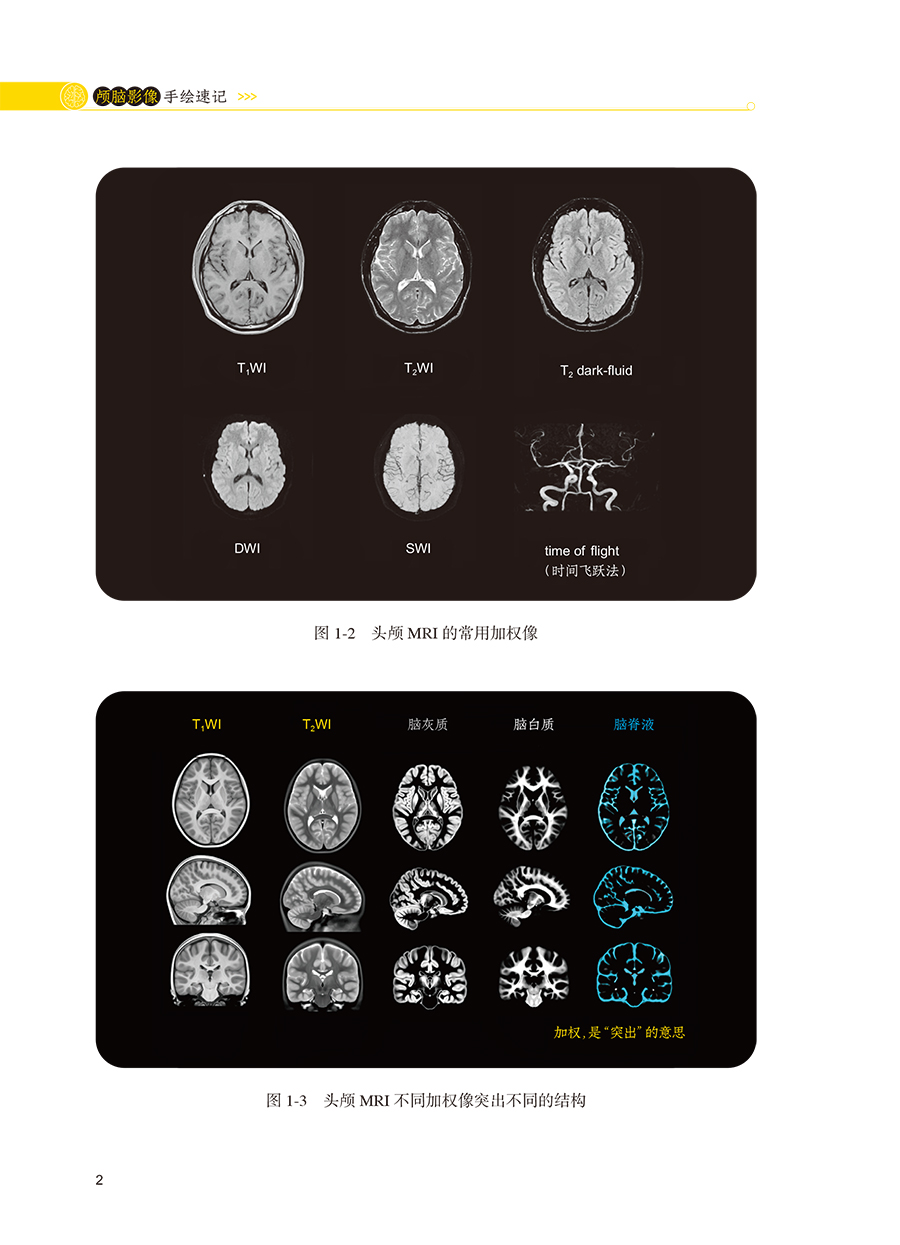

本书内容主要是精练的要点总结性文字和影像图联想记忆手绘的结合,分为正常颅脑影像篇和颅脑病变影像篇两大部分。正常颅脑影像部分主要包括正常生理状态下的颅脑CT和MRI成像特点介绍,及手绘记忆要点;颅脑病变影像手绘主要包括脑血管性疾病、颅内肿瘤、颅脑损伤、颅内感染性疾病、颅脑先天畸形、遗传性脑病、脱髓鞘疾病、癫痫、脑积水等各大疾病分类的CT和MRI影像学特征性表现、疾病发展不同时期的影像学变化特点总结,及手绘记忆要点。本书读者对象主要包括神经、急诊、重症医学、影像等科室医生及相关专业医学生。